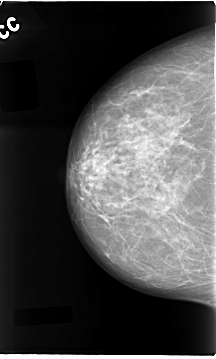

C_0087_1.RIGHT_CC

DATE_OF_STUDY 11 5 1994

PATIENT_AGE 58

FILM_TYPE REGULAR

DENSITY 2

RIGHT_CC LINES 4656 PIXELS_PER_LINE 2800 BITS_PER_PIXEL 12 RESOLUTION 50 NON_OVERLAY